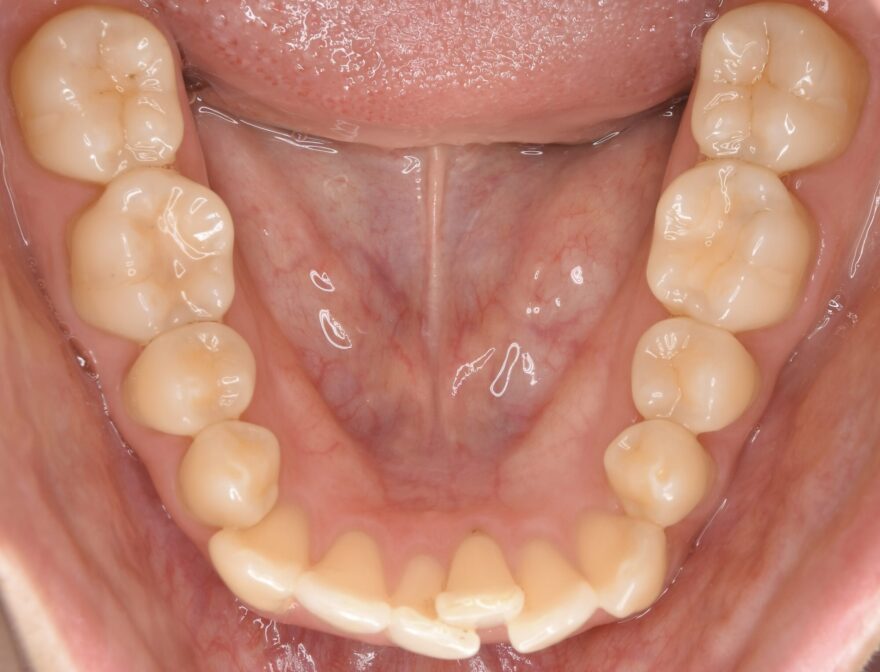

初診時の口腔内写真

同じように、2番目の前歯が、内側に引っ込んでいます。